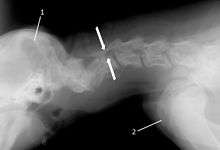

The disease tends to be gradually progressive. Symptoms such as weakness, ataxia, and dragging of the toes start in the rear legs. Dogs often have a crouching stance with a downward flexed neck. The disease progresses to the front legs, but the symptoms are less severe. Neck pain is sometimes seen. Symptoms are usually gradual in onset, but may progress rapidly following trauma.[6] X-rays may show misaligned vertebrae and narrow disk spaces, but it is not as effective as a myelogram, which reveals stenosis of the vertebral canal. Magnetic resonance imaging has been shown to be more effective at showing the location, nature, and severity of spinal cord compression than a myelogram.[7] Treatment is either medical to control the symptoms, usually with corticosteroids and cage rest, or surgical to correct the spinal cord compression. The prognosis is guarded in either case. Surgery may fully correct the problem, but it is technically difficult and relapses may occur. Types of surgery include ventral decompression of the spinal cord (ventral slot technique), dorsal decompression, and vertebral stabilization.[8] One study showed no significant advantage to any of the common spinal cord decompression procedures.[9] Another study showed that electroacupuncture may be a successful treatment for Wobbler disease.[10] A new surgical treatment using a proprietary medical device has been deveolped for dogs with disc-associated wobbler disease. It implants an artificial disc (cervical arthroplasty) in place of the affected disc space.[11]